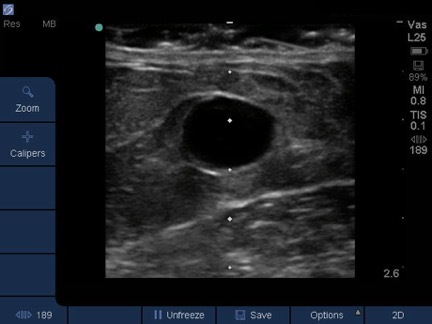

Dialysis Vessel Appearance Image